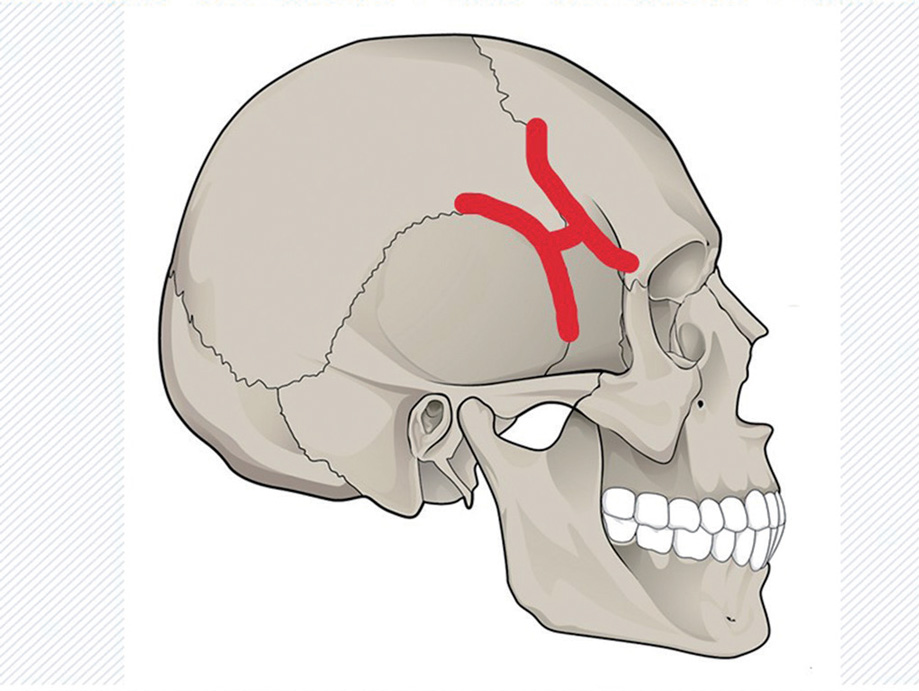

실제 부동관절은 한번 성장해서 성인이 되어 단단하게 붙으면 가동력이 거의 없기 때문에 거짓 관절이라고도 부릅니다. 하지만 심한 교통사고나 강한 망치 같은 것에 손상받을 경우 관절면이 떨어져서 탈구脫臼되면, 골절보다 더 심한 내부의 손상이 있을 수 있기 때문에 우리는 이 관절을 알아야 합니다.